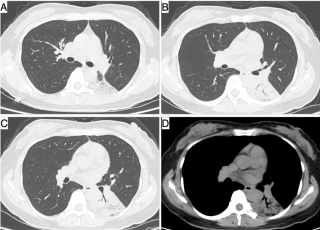

整个右侧胸腔被滚烫的铝水烧穿,多根肋骨骨折、碳化、坏死,背腹部和面部也有大面积烧伤……右肺完全暴露在外,被压缩到只剩一半的体积。这样的病人,还救得活吗?300℃ 铝水烧了 10 分钟,整个右胸都烧穿了时间拨回到 2024 年 9 月 26 日,下午 15 点,救护车的警笛声撕破了浙江大学医学院附属第二医院(文内简称「浙大二院」)解放路院区的平静。警笛声由远及近,停在了急诊的门口。不多时,一群人冲进急诊。「300 多度的铝水烧了 10 分钟,整个右胸都烧穿了!」负责转运的同事几乎是咆哮着喊出这句话。急诊医学科的许永安主任医师看到患者情形时,心下一惊。本该完整的右侧胸腔,现在成了一个焦黑的大洞,大